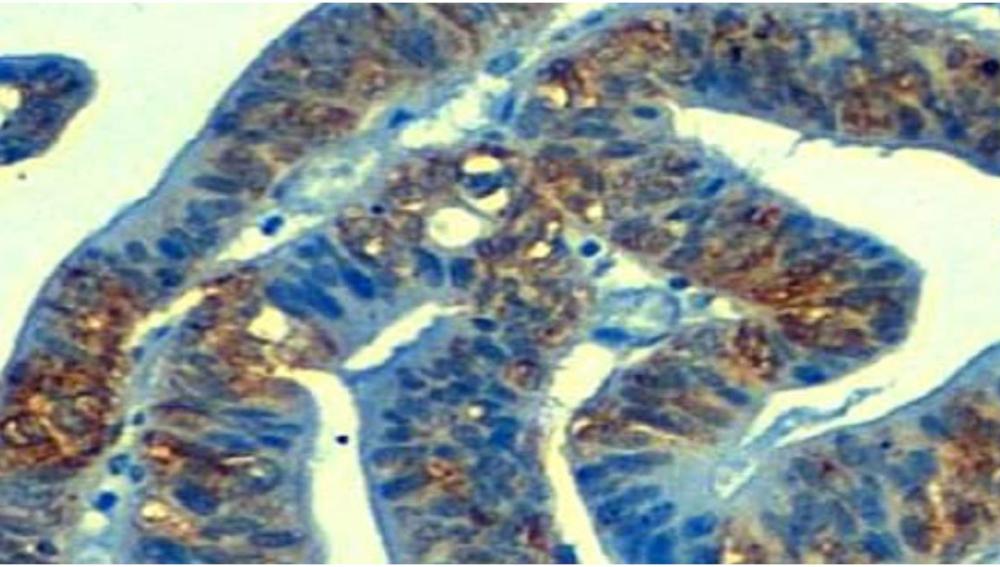

"Hemos encontrado que un 10% de tumores de colon y estómago presentan la pérdida de una molécula denominada TP53TG1, cuya función en células sanas es prevenir la activación de la proteína YBX1. Sin la vigilancia de TP53TG1 en estos tumores gastrointestinales, YBX1 se encarga de ir al núcleo de la célula y activar centenares de oncogenes que impedirán la muerte de las células malignas que inducen los fármacos antitumorales,” comenta Manel Esteller.